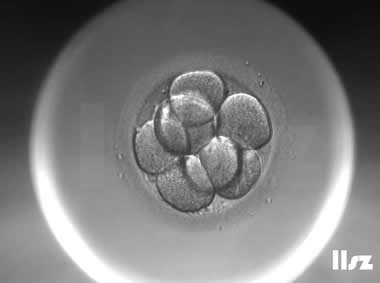

下面视频是胚胎在时差培养箱中培养至D3的整个过程,图片是D3(第68小时)的卵裂期胚胎图,本文D3胚胎评价是以D3时间点图片的形态学为依据,胚胎评级如下:

| Ⅱa级:该枚D3胚胎为8细胞,碎片在10%左右,因此评级为I级或Ⅱa级均可。 | |